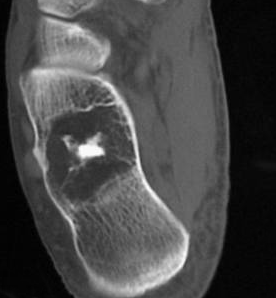

营养不良性钙化

营养不良性钙化为局部钙盐代谢异常所致的钙化。X 线平片和 CT 表现为无结构的不规则形致密影。良性肿瘤常见于骨内脂肪瘤(图 39),恶性骨肿瘤则常见于 PNET(图 40)和未分化多形性肉瘤。

图 39.营养不良性钙化:骨内脂肪瘤